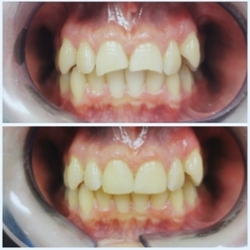

Dentalna protetika je grana dentalne medicine kojom nadomještamo izgubljene zube, korigiramo postojeće, poboljšavamo funkciju i estetski izgled zuba, a time i vašeg izgleda. Dijelimo je na fiksnu (krunice i mostovi) i mobilnu (parcijalne i totalne proteze).

Fiksna protetika podrazumijeva izradu krunica i mostova koji se fiksno cementiraju na zubima ili na implantatima.

Zubna krunica ili kako je ljudi vole zvati „navlaka“ je „kapica“ koja se radi na pojedinačnom zubu, bilo da je zub puknuo, promijenio boju ili ste jednostavno nezadovoljni njegovim izgledom. Također pojedinačna krunica može se napraviti i na implantatu, te se na njega fiksira cementiranjem ili vijkom.

Most je protetski nadomjestak kojim se nadoknađuje jedan ili više izgubljenih zubi, pri čemu se postojeći zubi koriste kao nosači mosta. Nosači mosta također mogu biti i implantati. Mostovi se, dakle, koriste kada želimo ispuniti prazninu nakon vađenja zuba (ako se ne odlučimo za implantate). Ukoliko se praznine između zubi ne saniraju adekvatnim rješenjem, riskiramo da se ostali zubi u ustima počnu pomicati, a to je samo korak do gubitka pravilnog zagriza i razvoja paradontoze.

U našoj ordinaciji najčešće radimo krunice odnosno mostove od ova 3 materijala:

Metal-keramičke krunice

U današnje vrijeme metal-keramičke krunice postale su standard zbog visoke čvrstoće i dugotrajnosti te zadovoljavajuće funkcije i estetike. Baza ove vrste krunice rađena je od metalne jezgre prekrivene keramikom. Metali koji se koriste za izradu uglavnom su zlatne legure, titanske legure ili kobalt-krom legure. Prednost metal-keramičkih krunica je velika čvrstoća metala koji je u bazi same krunice, ali sam metal joj je i nedostatak, jer je zbog njega estetika takve krunice lošija. Naime, metalna jezgra blokira prirodnu transluenciju zuba pa oni ne izgledaju priprodno zbog svog „mat efekta“,a s vremenom je moguća i pojava „tamne linije“ na rubovima uz zubno meso. Zbog svojih svojstava krunice odnosno mostove od ovog materijala preferiramo raditi na stražnjim zubima.

Cirkon-keramičke krunice

Cirkon-keramičke krunice kao što sam naziv kaže izrađuju se od cirkonske baze na koju se peče keramika. Cirkon-keramika poznata je po svojoj vrlo visokoj čvrstoći, stabilnosti, biokompatibilnosti i izvrsnoj estetici. Cirkon je kao materijal translucentan („prozračan“), što mu daje mogućnost imitacije prirodne boje zuba. Za razliku od metal-keramičkih krunica, cirkonska podloga ispod keramike je bijele boje pa ne može doći do prosijavanja metala uz rubove zubnog mesa, kao i obojenosti ruba zubnog mesa. Cirkon-keramičke krunice se izrađuju pomoću CAD/CAM tehnologije, te imaju visoku preciznost dosjeda. Izradu krunica od ovog materijala uvijek pacijentima sugeriramo za prednje zube zbog vrhunske estetike.

Cirkonske monolitne krunice

Cirkonske monolitne krunice su jednokomadne krunice izrađene od jedne vrste materijala. Monolitne krunice se izrađuju u potpunosti od cirkona, bez dodavanja keramičkog sloja. Kao i cirkon-keramičke krunice izrađuju pomoću CAD/CAM tehnologije koja rezultira visokom preciznošću dosjeda i najdetaljnijom morfologijom. Prednost monolita je veća brzina i preciznost izrade, a konačni rad karakteriziraju vrhunska estetika i funkcionalnost. Cirkonske monolitne krunice su uz to čvršće i otpornije na djelovanje žvačnih sila. Izradu ovakvih krunica predlažemo pacijentima za prednje kao i stražnje zube.

Postupak izrade krunica

Prije početka bilo kakvih radova u ustima potrebno je napraviti ortopan snimku da bi se uočile eventualne upale na zubu, neadekvatni endodontski zahvati ili upale zubnog mesa. Nakon sanacije takvih nedostataka zubi se bruse i uzimaju se otisci.

Izrađuju se privremeni zubi kako ne bi morali odlaziti kući bez zuba. Oni se izrađuju na temelju otisaka prije početka terapije, a može ih napraviti doktor dentalne medicine u ordinaciji ili dentalni tehničar u zubnom laboratoriju.

Slijedi faza probe zubi i završna faza cementiranja (ljepljenja krunica ili mostova). Čitav postupak traje 7-10 dana.

Trajanje fiksnoprotetskih nadomjestaka ovisi o oralnoj higijeni pacijenta, te o redovitim posjetima doktoru dentalne medicine barem dva puta godišnje.